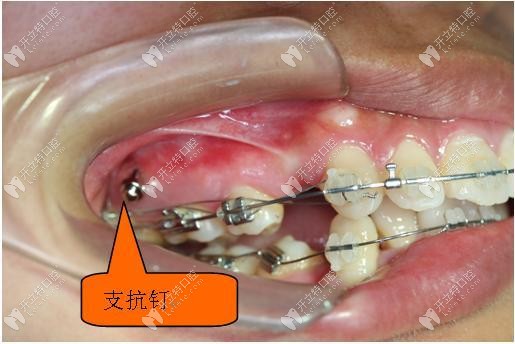

矯正中所需要的骨釘

口腔種植體支抗是將純鈦制作的特殊的微小鈦釘植入到患者的上頜后牙區(qū)、下頜后牙區(qū)、硬腭部,牙齒槽間隔等等的部位,利用這種植入的微小鈦釘作正畸治療的支抗,牽引排列不齊的牙齒作移動(dòng),從而達(dá)到矯治牙列不齊的目的。

支抗釘在矯正過(guò)程中可適用的位置